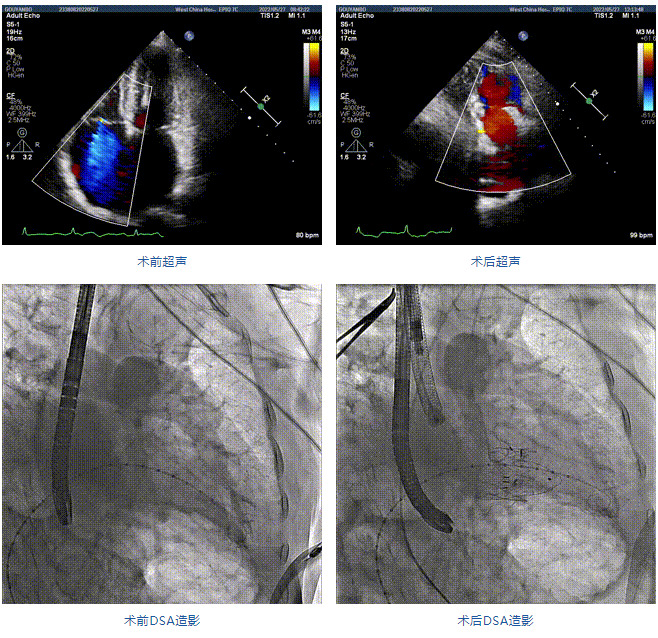

2022年5月27日,四川大學(xué)華西醫(yī)院心臟內(nèi)科陳茂、馮沅教授帶領(lǐng)的瓣膜病介入治療多學(xué)科團(tuán)隊(duì),在國(guó)內(nèi)首次采用純介入方式通過穿刺右側(cè)頸靜脈成功完成經(jīng)導(dǎo)管三尖瓣置換。植入的人工瓣膜是具有中國(guó)自主知識(shí)產(chǎn)權(quán)的LuX-Valve Plus系統(tǒng)。術(shù)中上海長(zhǎng)海醫(yī)院陸方林教授和喬帆副教授給予了在線支持。

患者為89歲高齡男性,罹患三尖瓣反流多年,近期癥狀明顯加重,經(jīng)過充分的藥物治療后仍然存在嚴(yán)重心力衰竭。通過純介入方式實(shí)施三尖瓣置換,使這位超高齡的老人以最小的代價(jià)獲得了有效的治療。介入治療的效果十分滿意,術(shù)后三尖瓣反流消除,老人迅速恢復(fù),心功能明顯改善。該手術(shù)的成功實(shí)施標(biāo)志著國(guó)內(nèi)經(jīng)導(dǎo)管三尖瓣置換進(jìn)入純介入時(shí)代。

89歲男性。術(shù)前超聲報(bào)告顯示:雙房增大,左室壁肥厚,主、肺動(dòng)脈增寬,三尖瓣重度反流。

團(tuán)隊(duì)前期經(jīng)過多次討論,制定了周密的手術(shù)策略和預(yù)案。由于患者已是近九旬的超高齡老人,傳統(tǒng)外科開胸手術(shù)風(fēng)險(xiǎn)極高,純介入經(jīng)血管三尖瓣替換能夠明顯減少創(chuàng)傷。術(shù)中陳茂及馮沅教授結(jié)合體表定位在造影指示下精準(zhǔn)穿刺右側(cè)頸靜脈并預(yù)置兩把血管縫合器。成功建立經(jīng)皮血管入路后在食道超聲和DSA的引導(dǎo)下順利完成人工瓣膜植入,術(shù)后超聲和造影顯示人工三尖瓣同軸性良好,瓣架固定牢靠,無反流和瓣周漏,平均跨瓣壓差降為1mmHg。術(shù)畢收緊預(yù)置的血管縫合器縫線完成止血,縫合效果滿意,在手術(shù)室即刻拔除氣管插管。